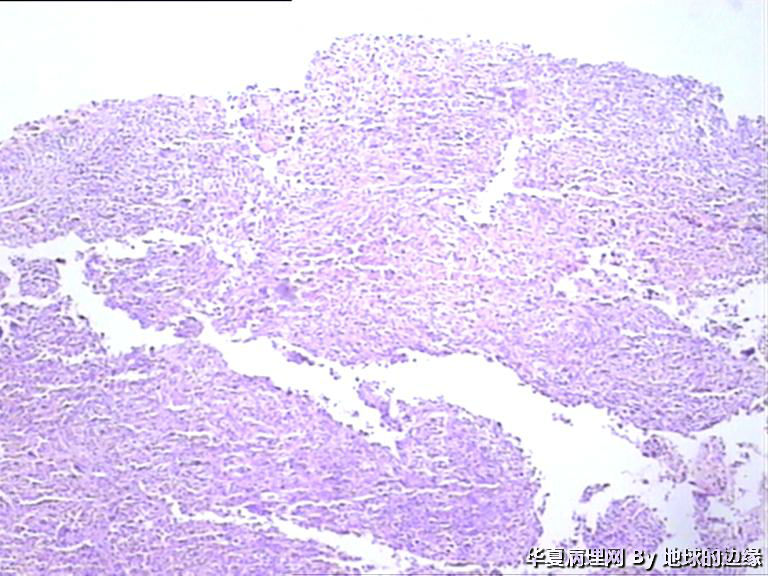

病人女性,48岁

MRI示:右肱骨肿瘤待排,包块大小为10x8cm,活动度差,边界欠清,鱼肉组织(白色),肿块侵犯至骨外    组  织。

• 右肱骨肿瘤待查图4

图4

恶性。是转移还是原发,是骨肉瘤还是浆母?需要进一步资料并标记。

考虑肉瘤,转移癌也排除一下吧